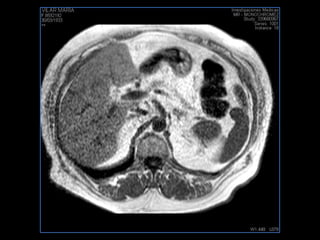

PROTOCOLO hígado graso AXIAL in phase y out phase AX T1 y AX fat sat +SAG T2  CON   GADOLINIO :  COR T1+AX T1(DIN) SAT: NO  FASE: RL THK: 4MM  COIL:  GAP: (FACTOR 1.4)  FOV: 40 CM NEX:2 SINCRONIZACION RESPIRATORIA EN 3 O 4 CICLOS ALE

PROTOCOLO hemocromatosis AXIAL supresión grasa /AX multieco en higado COR T2 AX T1 +SAG T2  CON   GADOLINIO :  COR T1+AX T1 SAT: NO  FASE: RL THK: 4MM  COIL:  GAP: (FACTOR 1.4) 1MM FOV: 40 CM NEX:2 SINCRONIZACION RESPIRATORIA EN 3 O 4 CICLOS ALE

PROTOCOLO pancreas/ riñon AXIAL fat sat /AX in phase out phase AX T1 +SAG T2  COR T2, CON   GADOLINIO :  COR T1+AX T1(DIN) SAT: NO  FASE: RL THK: 4MM  COIL:  GAP: (FACTOR 1.4) 1MM FOV: 40 CM NEX:2 SINCRONIZACION RESPIRATORIA EN 3 O 4 CICLOS ALE

resonancia de abdomen